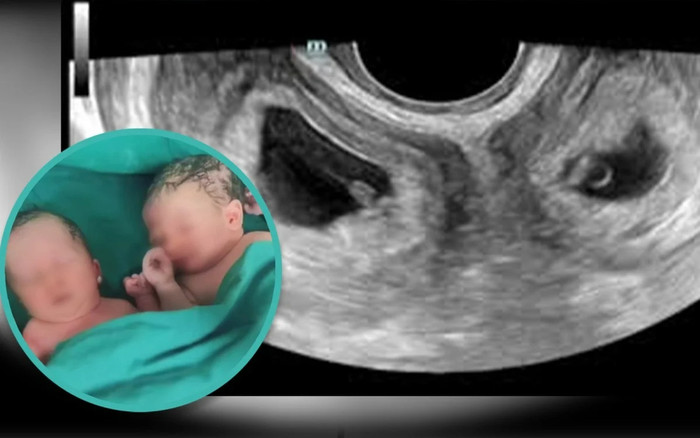

Người phụ nữ sinh đôi một trai một gái dù gặp phải tình trạng tử cung đặc biệt.

Người phụ nữ họ Li này mắc phải tình trạng chỉ xuất hiện trên 0,3% phụ nữ toàn thế giới. Cả hai tử cung của cô đều đã hình thành đầy đủ và bao gồm cả buồng trứng và ống dẫn trứng, theo Đài phát thanh quốc gia Trung Quốc. Tình trạng buồng trứng đôi rất hiếm gặp, nhưng việc phụ nữ sinh con thành công thậm chí còn hiếm gặp hơn.

Li đã sinh đôi một bé trai và một bé gái vào đầu tháng 9 tại Bệnh viện số 4 Tây An, tỉnh Thiểm Tây khi cô đang mang thai được tám tháng rưỡi.

Cai Ying, một bác sĩ sản khoa cao cấp tại bệnh viện, được trích dẫn như sau: "Việc mang thai ở mỗi tử cung thông qua thụ thai tự nhiên là rất hiếm. Chúng tôi chỉ nghe nói về một vài trường hợp như vậy ở cả Trung Quốc và nước ngoài".

Bà nói thêm: "Thậm chí còn hiếm hơn khi một phụ nữ mắc chứng bệnh này có thể sinh con thành công sau 37 tuần", đồng thời nói thêm rằng đây là hiện tượng "có một trên một triệu".

Sau khi Li mang thai vào tháng 1, các bác sĩ tại bệnh viện Tây An đã vạch ra một kế hoạch tỉ mỉ để đảm bảo an toàn cho cô. Các em bé chào đời khỏe mạnh, bé trai nặng 3,3kg và bé gái nặng 2,4kg. Các bác sĩ đã tiến hành phẫu thuật lấy thai trong khi sinh. Li và những đứa con mới sinh của cô được xuất viện bốn ngày sau khi sinh.

Tình trạng có hai buồng trứng khá hiếm gặp và thậm chí còn bất thường hơn khi một người phụ nữ có thể sinh con thành công ở cả hai bên. Ảnh: Douyin